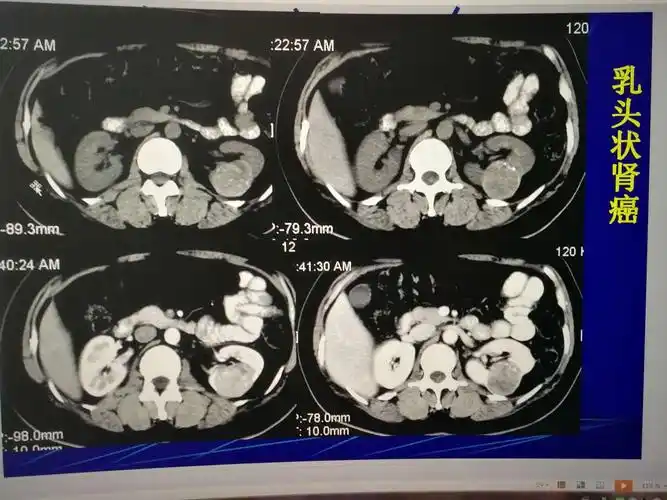

囊性肾癌的ct诊断

8cm,肿瘤增强后明显强化,考虑为肾癌,未见肿大淋巴结,未见肾脏静脉瘤